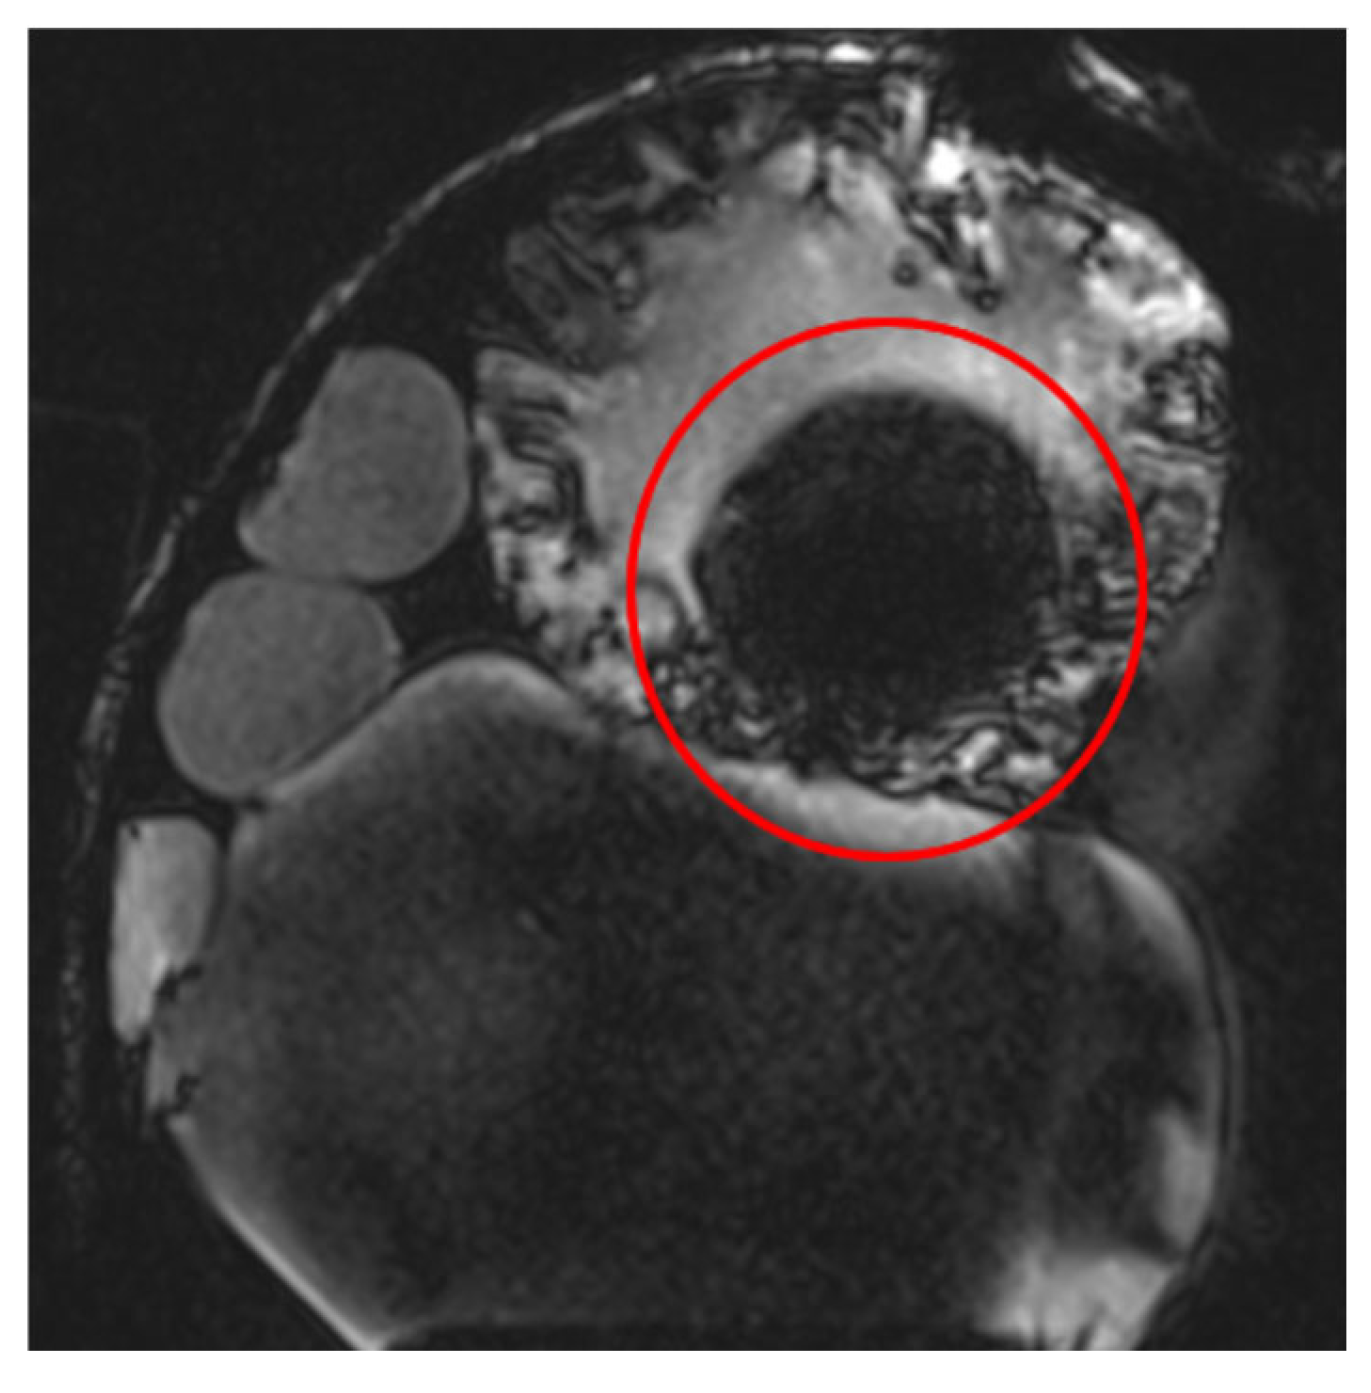

RF pulse inhomogeneity can arise due to coil design and signal reception inconsistencies, leading to unwanted spatial signal variations within the image. Differences in local RF flip angles depend on both scanner calibration and RF energy distribution. One disadvantage of high-field MRI (3 T and above) is increased image inhomogeneity caused by RF wave interference within the scanned volume. At higher frequencies, the RF wavelength becomes comparable to the size of scanned structures (e.g., tissues or materials), leading to destructive interference, signal loss in some areas, and signal amplification in others. This effect is clearly visible (Figure 4) in the t1_vibe_fs_tra sequence and t2_tse_fs_tra sequence.

Figure 4.

Effects of RF pulse inhomogeneity and high-field interference on signal distribution (a) t1_vibe_fs_tra sequence showing pronounced destructive RF interference and signal dropout, indicated by the red arrow (b) t2_tse_fs_tra sequence illustrating spatial signal amplification and central inhomogeneity.